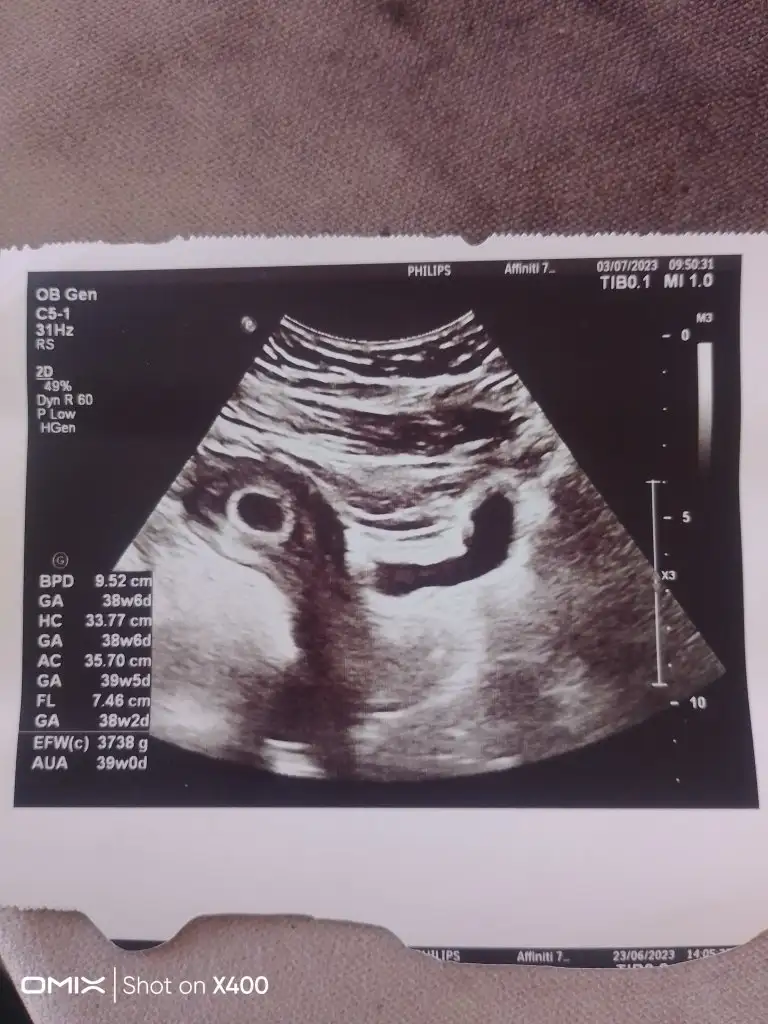

Ay çok sevindim canım ya hep te seninle olur inşallahEvet sukurler olsun canım devletteki doktor kan uyuşmazlığı iğnesi verdi. Bebek biraz aşağıda dedi. 6+1 gördü bebeği 7+0 bugün normalde. Ama 6+6 da olabilir adetim gece geç gelmiş takvime öyle işaretlemiş olabilirim. Doktor kalp atışını duydu, gösterdi, ben de duydum. İşte burda dedi. Çok güzel ritmik dedi. Progestan yazdı. Betayi onemsemiyoruz artık dalgalanmasini. Bebek önemli dedi. Şok icersindeyim. Minik mucizem benimle. Doktora gidicem yine özele 2 de dua edin nolur